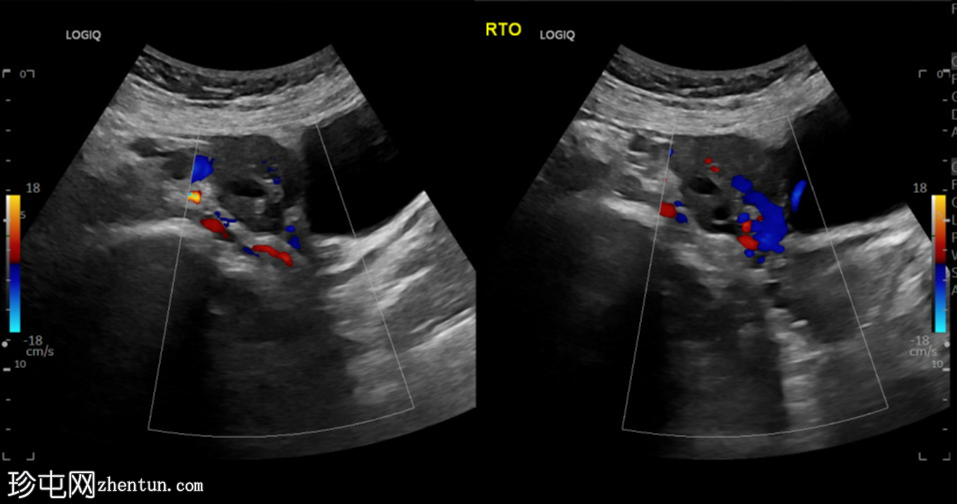

超声检查

纵切面

左侧卵巢明显增大,可见一囊肿,大小约3.2 x 2.3 cm,呈火环征,可能为黄体囊肿。左侧卵巢与子宫之间可见一管状结构,直径约1.3 cm,内含浑浊液体,未见血管,最可能为输卵管积血。以上特征提示可能为左侧异位妊娠。

未见宫内妊娠囊。